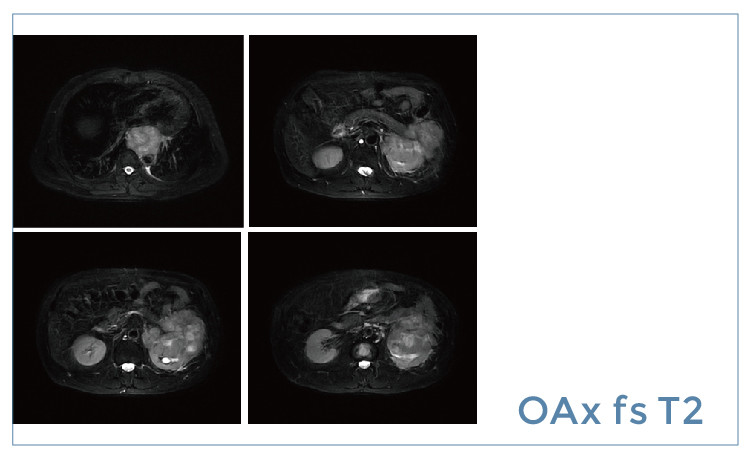

【朗润影像档案】20190419磁共振影像病例结果讨论

【朗润影像档案】磁共振影像病例分享(编号20190419)